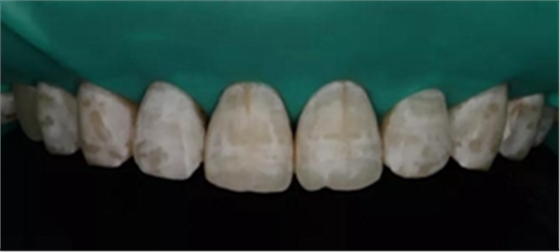

4、使用ICON無水乙醇預見顏色

如果預見顏色個別位置還有黃色斑塊 只需要鹽酸重新酸蝕斑塊位置兩分鐘,增加效果。

無水乙醇干燥后